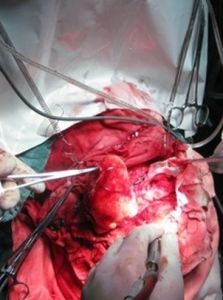

手術治療外科手術為顱咽管瘤的首選治療方法。手術治療的目的是通過切除腫瘤達到解除腫瘤對視神經交叉及其他神經組織的壓迫,解除顱內壓增高,對下丘腦-垂體功能障礙則較難恢復。對於實質性腫瘤,手術可切除瘤體;對於囊性腫瘤,手術可放去囊液,從而緩解腫瘤的壓迫症狀。由於顱咽管瘤為良性腫瘤,除部分與視交叉、灰結節、垂體柄、下丘腦、第三腦室底等某處粘連外,大多數與周圍組織結構有膠質反應邊界或蛛網膜分界,因此原則上應力爭做到腫瘤全切除,尤其對兒童患者,以防止復發。小的顱咽管瘤特別是鞍內型腫瘤一般採取經蝶術式,大瘤宜採取經顱術式。一般來說,成功的手術可有效緩解視交叉受壓引起的視力、視野改變以及高顱壓引起的頭痛等症狀,還能使腺垂體功能得到恢復。不過,很多鞍上型顱咽管瘤與周圍腦組織(特別是下丘腦)緊密相連,增加了手術的難度,對這些病人並不強求完全切除腫瘤,可採取部分切除,部分切除的缺點是術後復發率很高。根據腫瘤生長部位、大小、形狀、鈣化程度、囊腫部分的位置,以及與周圍組織的關係和容易接近腦脊液通路等因素,手術需選擇不同的入路或方式,並各自有其優缺點。